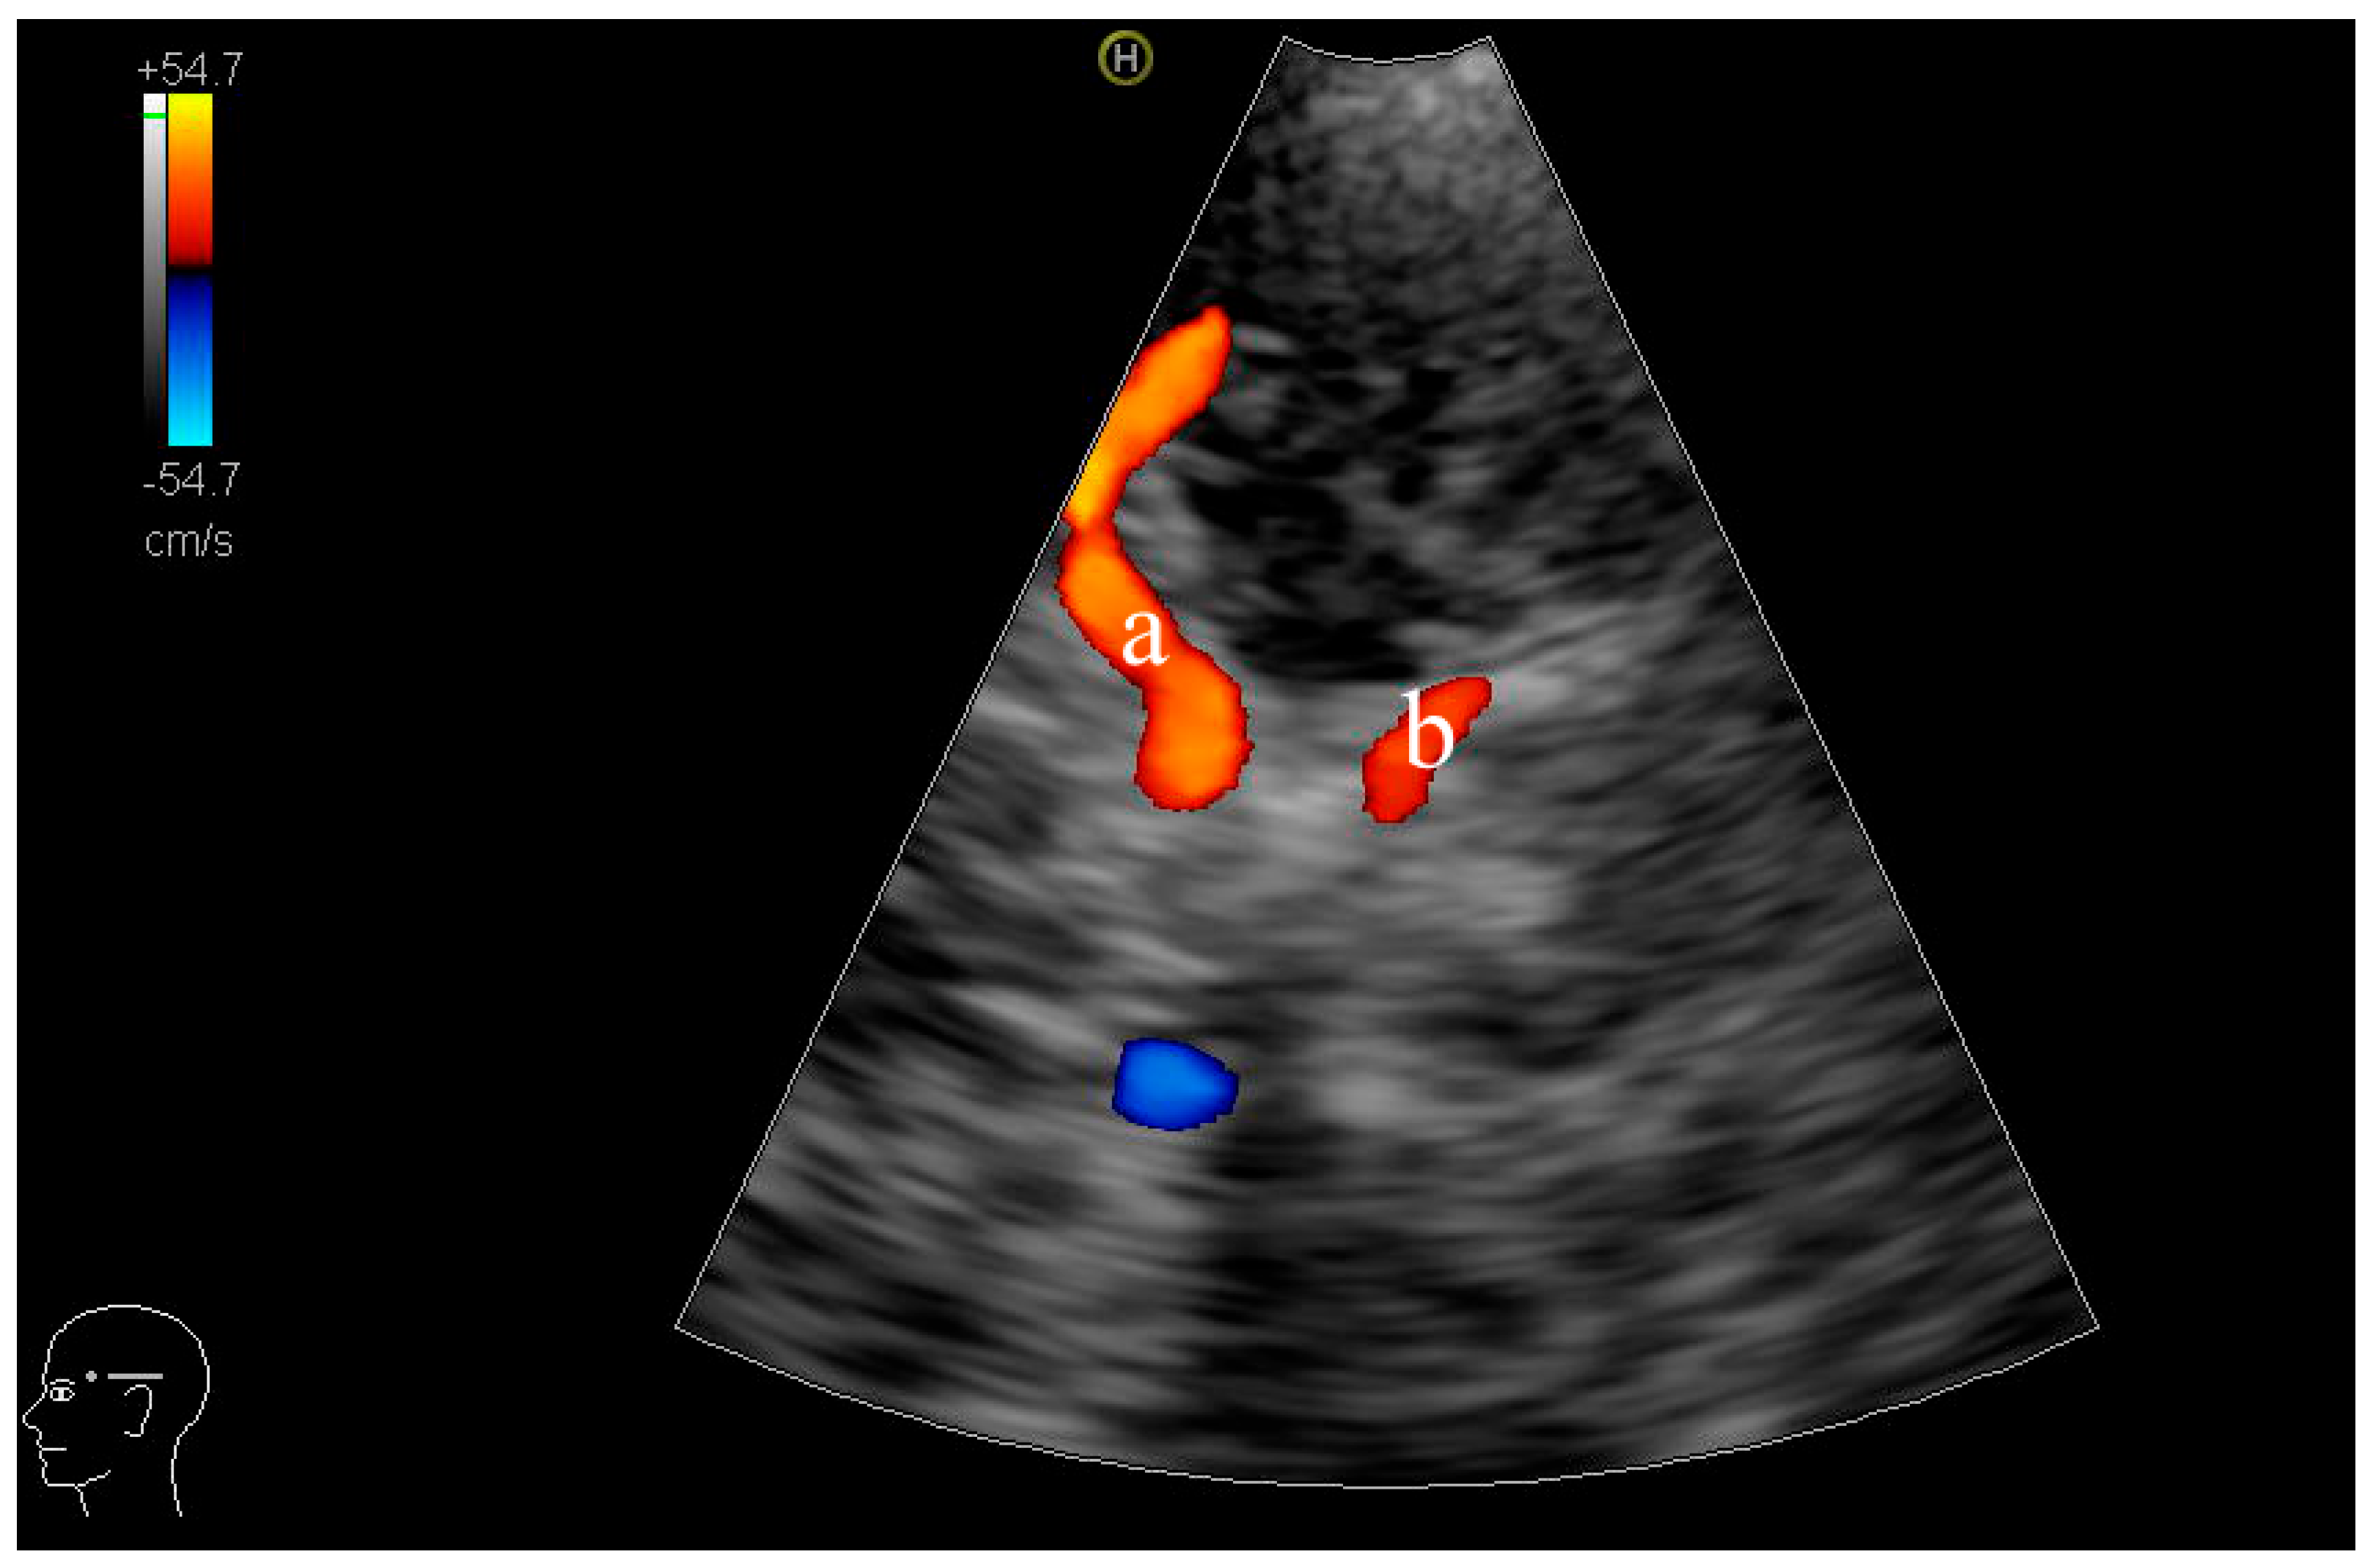

2.2. Equipment and Patient Positioning

2.3. TCCD Examination Procedure